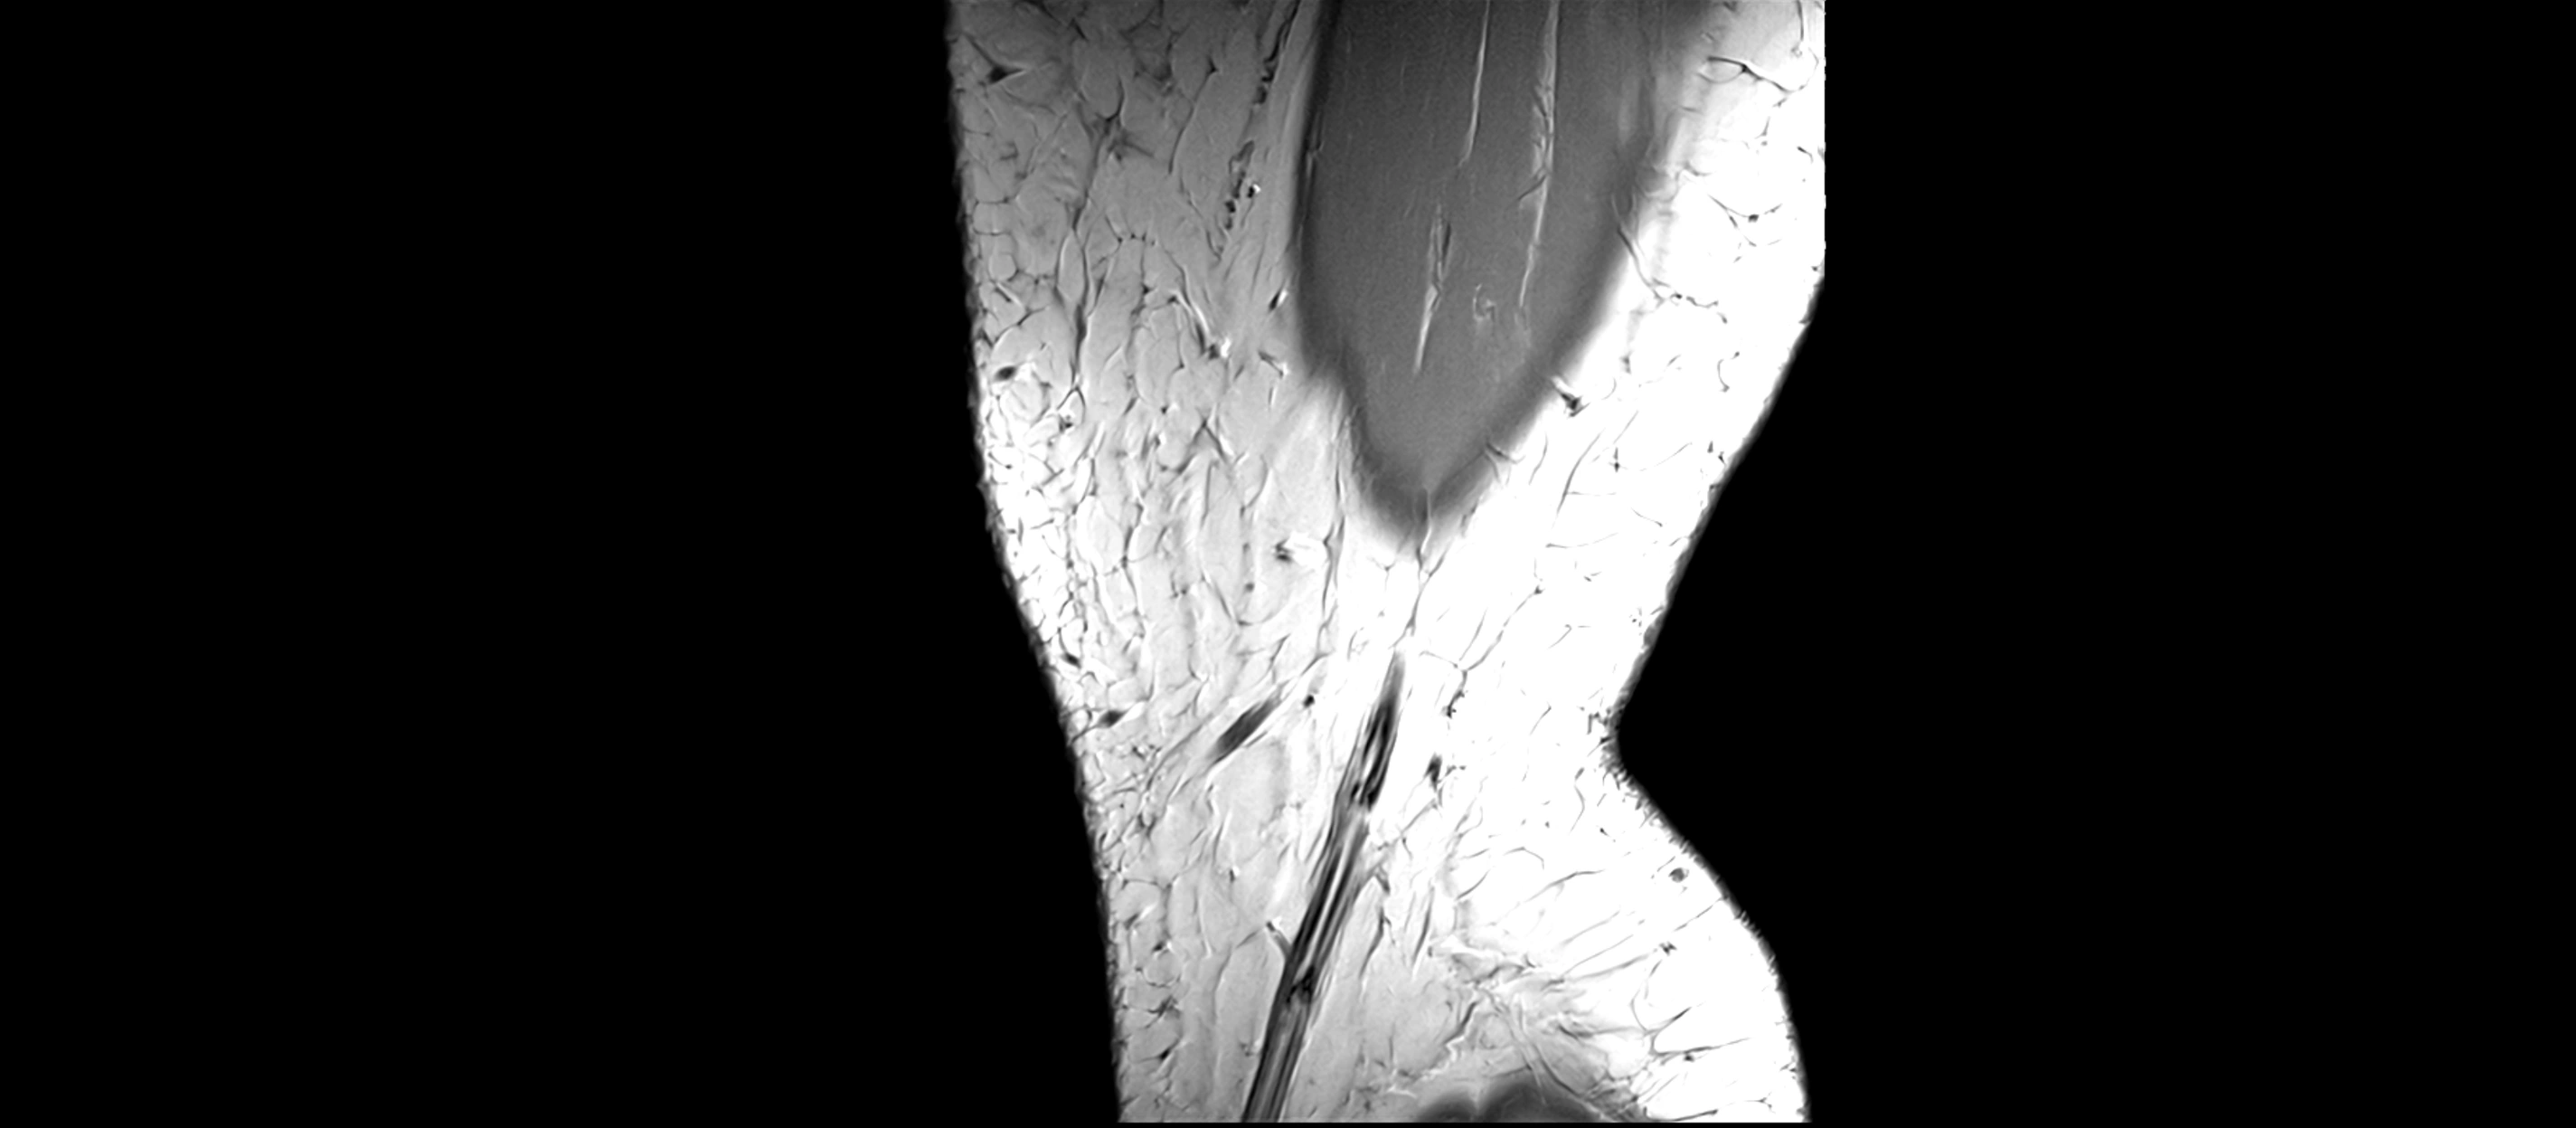

MRI Appearance

T2-weighted images:

• Normal ACL remains low signal

• Partial or complete tears appear as discontinuity, increased signal, or fiber laxity

MRI images

image